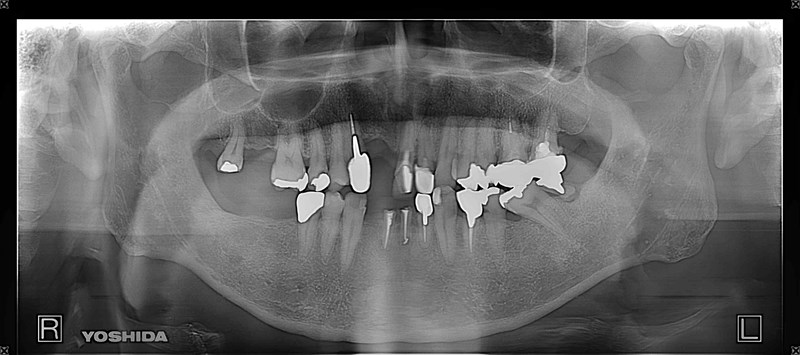

症例140代 男性 主訴 左右臼歯部欠損の為、奥歯で噛めない 前歯がグラつく

治療前

治療後

奥歯でしっかり噛めるようにインプラントを計画・提案。

前歯の長いブリッジは力学的に負担がある為、支えとなるインプラントを配置。

右上小・大臼歯部は、骨高不足の為、ソケットリフト(上顎洞洞底膜挙上術)を適用。

約5ヶ月間の治療期間を経て、全てジルコニアを装着し終了。

リスクとしては外科的侵襲がある。デメリットは、保険外診療の為、経済的負担がある。

費用 340万(税込)(オペ・仮歯・最終補綴物まで含む)